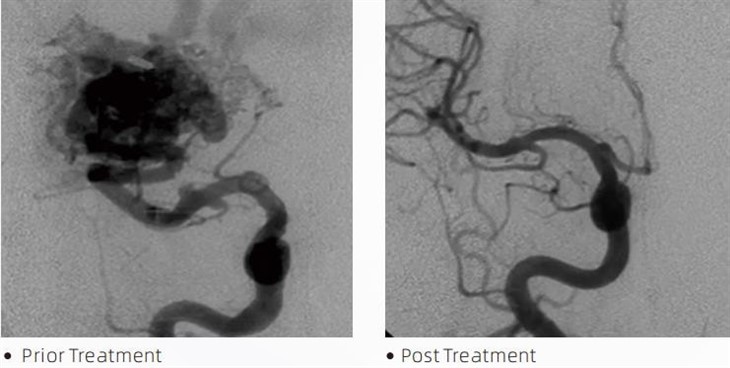

LavaTMgam embolik ialah peranti perubatan yang digunakan oleh pakar neuroradiologi intervensi semasa prosedur invasif minimum untuk merawat keadaan seperti aneurisma serebrum, kecacatan arteriovenous dan tumor. Gam emboli Lava menawarkan pelbagai faedah kepada profesional perubatan dan pesakit dari segi keselamatan, kemudahan penggunaan dan keberkesanan. Lava mampu menutup saluran darah dengan cepat dan cekap. Proses ini melibatkan suntikan gam terus ke dalam bekas yang disasarkan, di mana ia mempolimer dan mengeras menjadi jisim seperti tuangan yang mengisi aneurisme atau kecacatan. Kemudian ia secara berkesan memotong aliran darah ke lesi, menghalangnya daripada pecah dan mengurangkan risiko kerosakan kekal atau strok. Lava termasuk Lava-12, Lava-18 dan Lava-34. Setiap formulasi direka untuk memenuhi keperluan klinikal tertentu. Lava-18 ialah rumusan standard untuk kegunaan umum. Lava-34 ialah gam berkelikatan tinggi untuk bejana aliran tinggi. Walaupun Lava-12 mempunyai kelikatan yang lebih rendah dan lebih mudah mengalir, membenarkan saluran mikro distal. Dengan pilihan ini, pakar neuroradiologi intervensi boleh memilih formulasi Lava yang sesuai untuk memastikan hasil yang optimum. Salah satu ciri Lava yang paling luar biasa ialah sifat bukan pelekatnya. Bahan ini dirumus khas untuk kekal stabil sehingga mencapai kawasan sasaran. Ciri ini bermakna gam embolik Lava boleh diletakkan dengan tepat di dalam arteri dan kekal di sana tanpa melekat atau terikat pada tisu sekeliling.